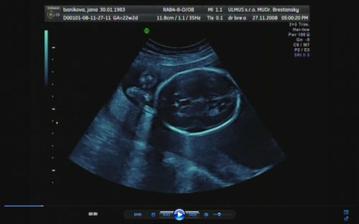

30.10.2008 - výsledky skríningových testov dopadli na jednotku, veľmi sa tešíme a dňa *****27.11.2008 - sme sa objednali na 3D ultrazvuk, tak som zvedavá, či nám potvrdia dievčatko a uvidím to na vlastné oči ... všetkým sa akosi zdá, že to bude chlapec 🙂 ....

Tak a máme to za sebou, náš 3D ultrazvuk, na ktorý sme sa moc moc tešili, bolo to úžasné, naša bambula Simonka sa nám ukázala v plnej kráse, akurát si zakrývala tváričku a nie a nie sa nám ukázať ... ale pár fotiek sa predsa len podarilo..pán doktor všetko prezrel a zatiaľ sa všetko vyvíja tak ako má .....